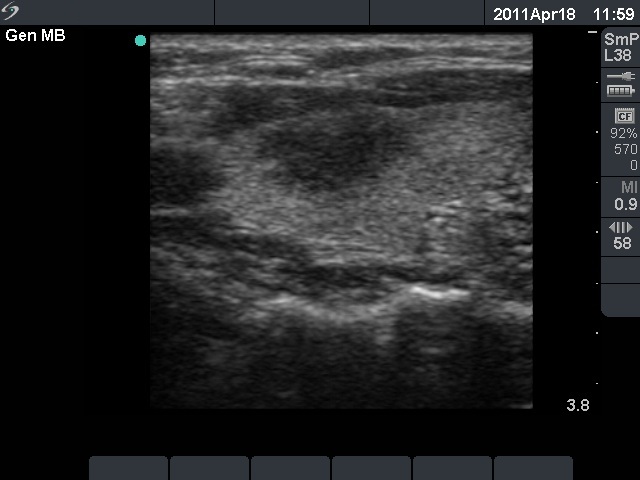

The relapse of de Quervain's thyroiditis in the contralateral lobe is a very frequent finding but not one year after the appearance of the disease. We supposed that the immunological changes during and after pregnancy explained the relatively late relapse of the disease.